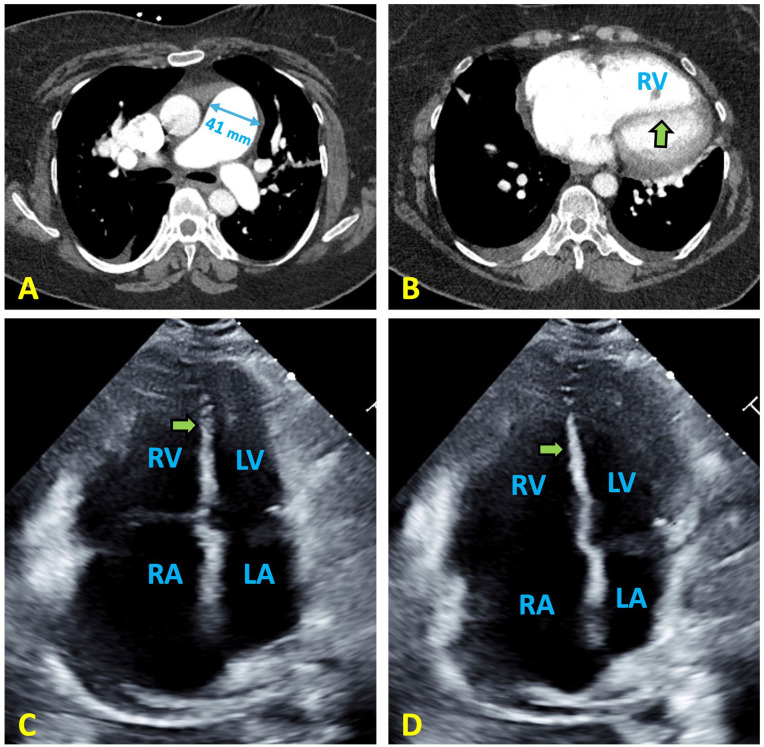

Partial anomalous pulmonary venous return (PAPVR) involving the left upper lobe pulmonary vein is an exceptionally rare congenital anomaly that, if untreated, can lead to pulmonary hypertension (PH). Its nonspecific clinical presentation often results in delayed diagnosis. We report the case of a 58-year-old woman who initially presented with progressive dyspnea and was diagnosed with group III pulmonary hypertension attributed to obstructive lung disease. Two years later, she returned with similar symptoms after discontinuing diuretic therapy. Further evaluation uncovered a previously undetected anomalous left pulmonary vein draining into the left innominate vein. This case highlights the diagnostic challenges of PAPVR, its role in contributing to PH, and the critical need for high clinical suspicion and comprehensive evaluation in patients with unexplained pulmonary hypertension.